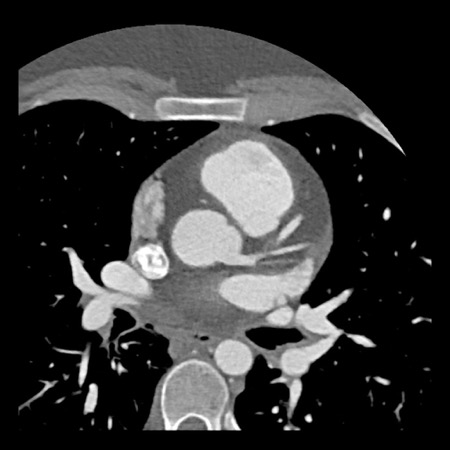

case 4 – CAD-RADS 3/P1/I+ thrombus left ventricle

First, scroll through the CTA images.

How would you describe the findings on the coronary CTA?

The findings are:

- Moderate (50-69%)

stenosis in the proximal LAD caused by a non-calcified plaque. - Variant of

sinoatrial (SA) nodal artery. The artery usually arises from the RCA as a second

branch after the conus artery, however in this case it arises from the LCX,

courses behind the aorta, anastomosing with the right atrium and with a small

branch supplies the SA-node of the heart. - Thrombus in the

apex of the left ventricle. - CTP was performed

in this patient. CTP showed a perfusion defect at stress imaging in the

territory of the LAD (I+), at rest no perfusion defect was visible.

This patient classifies as CAD-RADS 3/P1/I+, which means

this patient requires further investigation.

…

Same patient.

A: Curved MPR of the LAD with non-calcified plaque causing moderate (50-69%) stenosis.

B: The so-called “spider-view” (LAO caudal) of the heart with a 70% stenosis in the proximal LAD. Note the presence of SA nodal artery arising from the proximal LCX and coursing to posterior direction.

C: A drug eluting stent (DES) was implanted into the proximal LAD with good results.